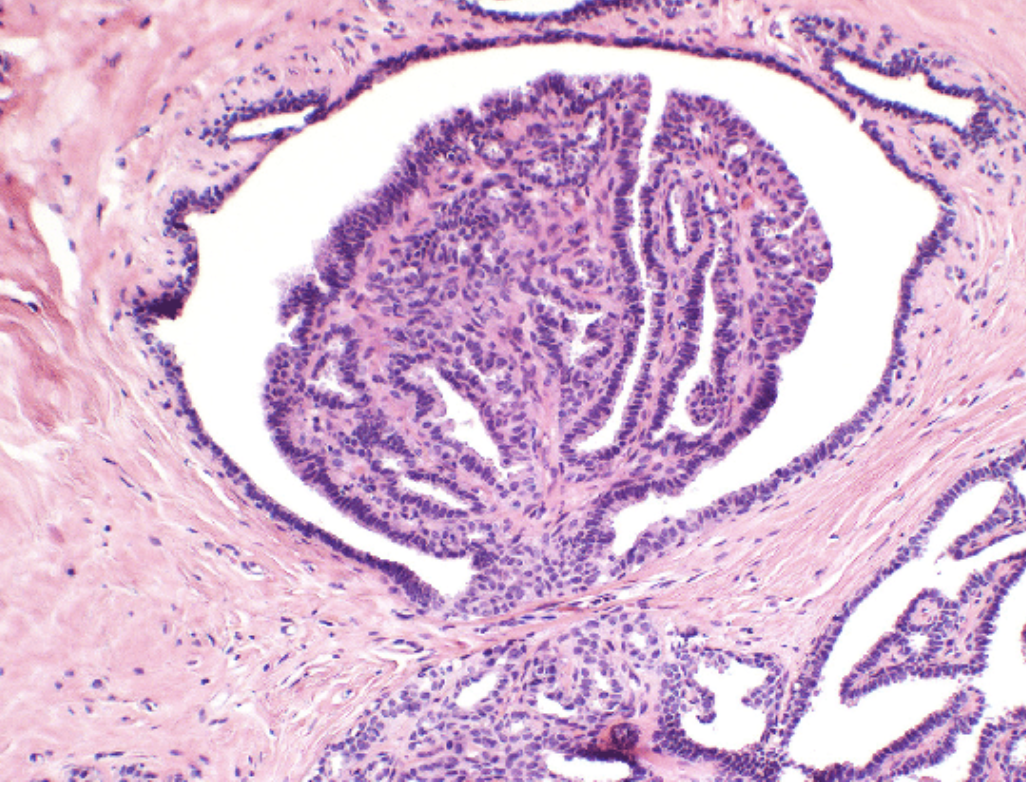

Intaductal Papilloma

Benign papillary tumour arising within the duct system of the breast (from the laciferous ducts)

Clinically presents with a sub-areolar mass +/- bloody nipple discharge

1. Not seen on mammogram.

2. Cytology of nipple discharge – branching papillary groups of epithelium

• Histology – papillary mass within a dilated duct lined by epithelium